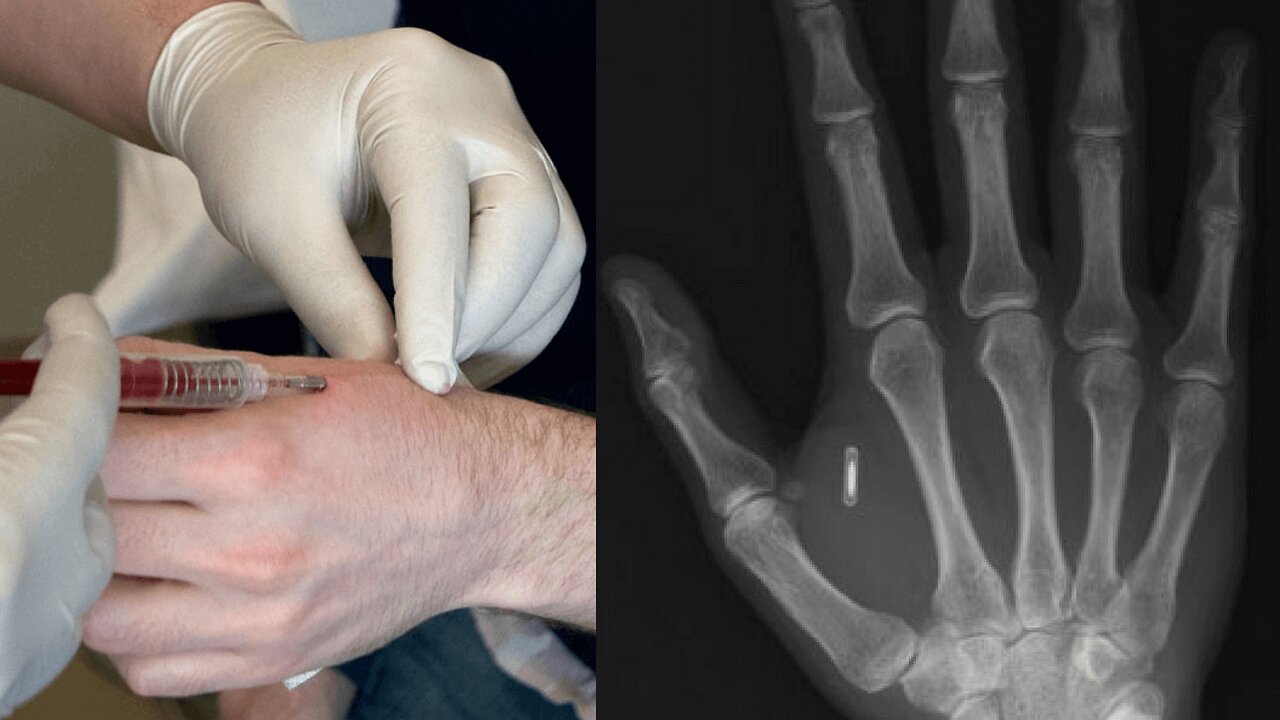

What Is The Mark Of The Beast